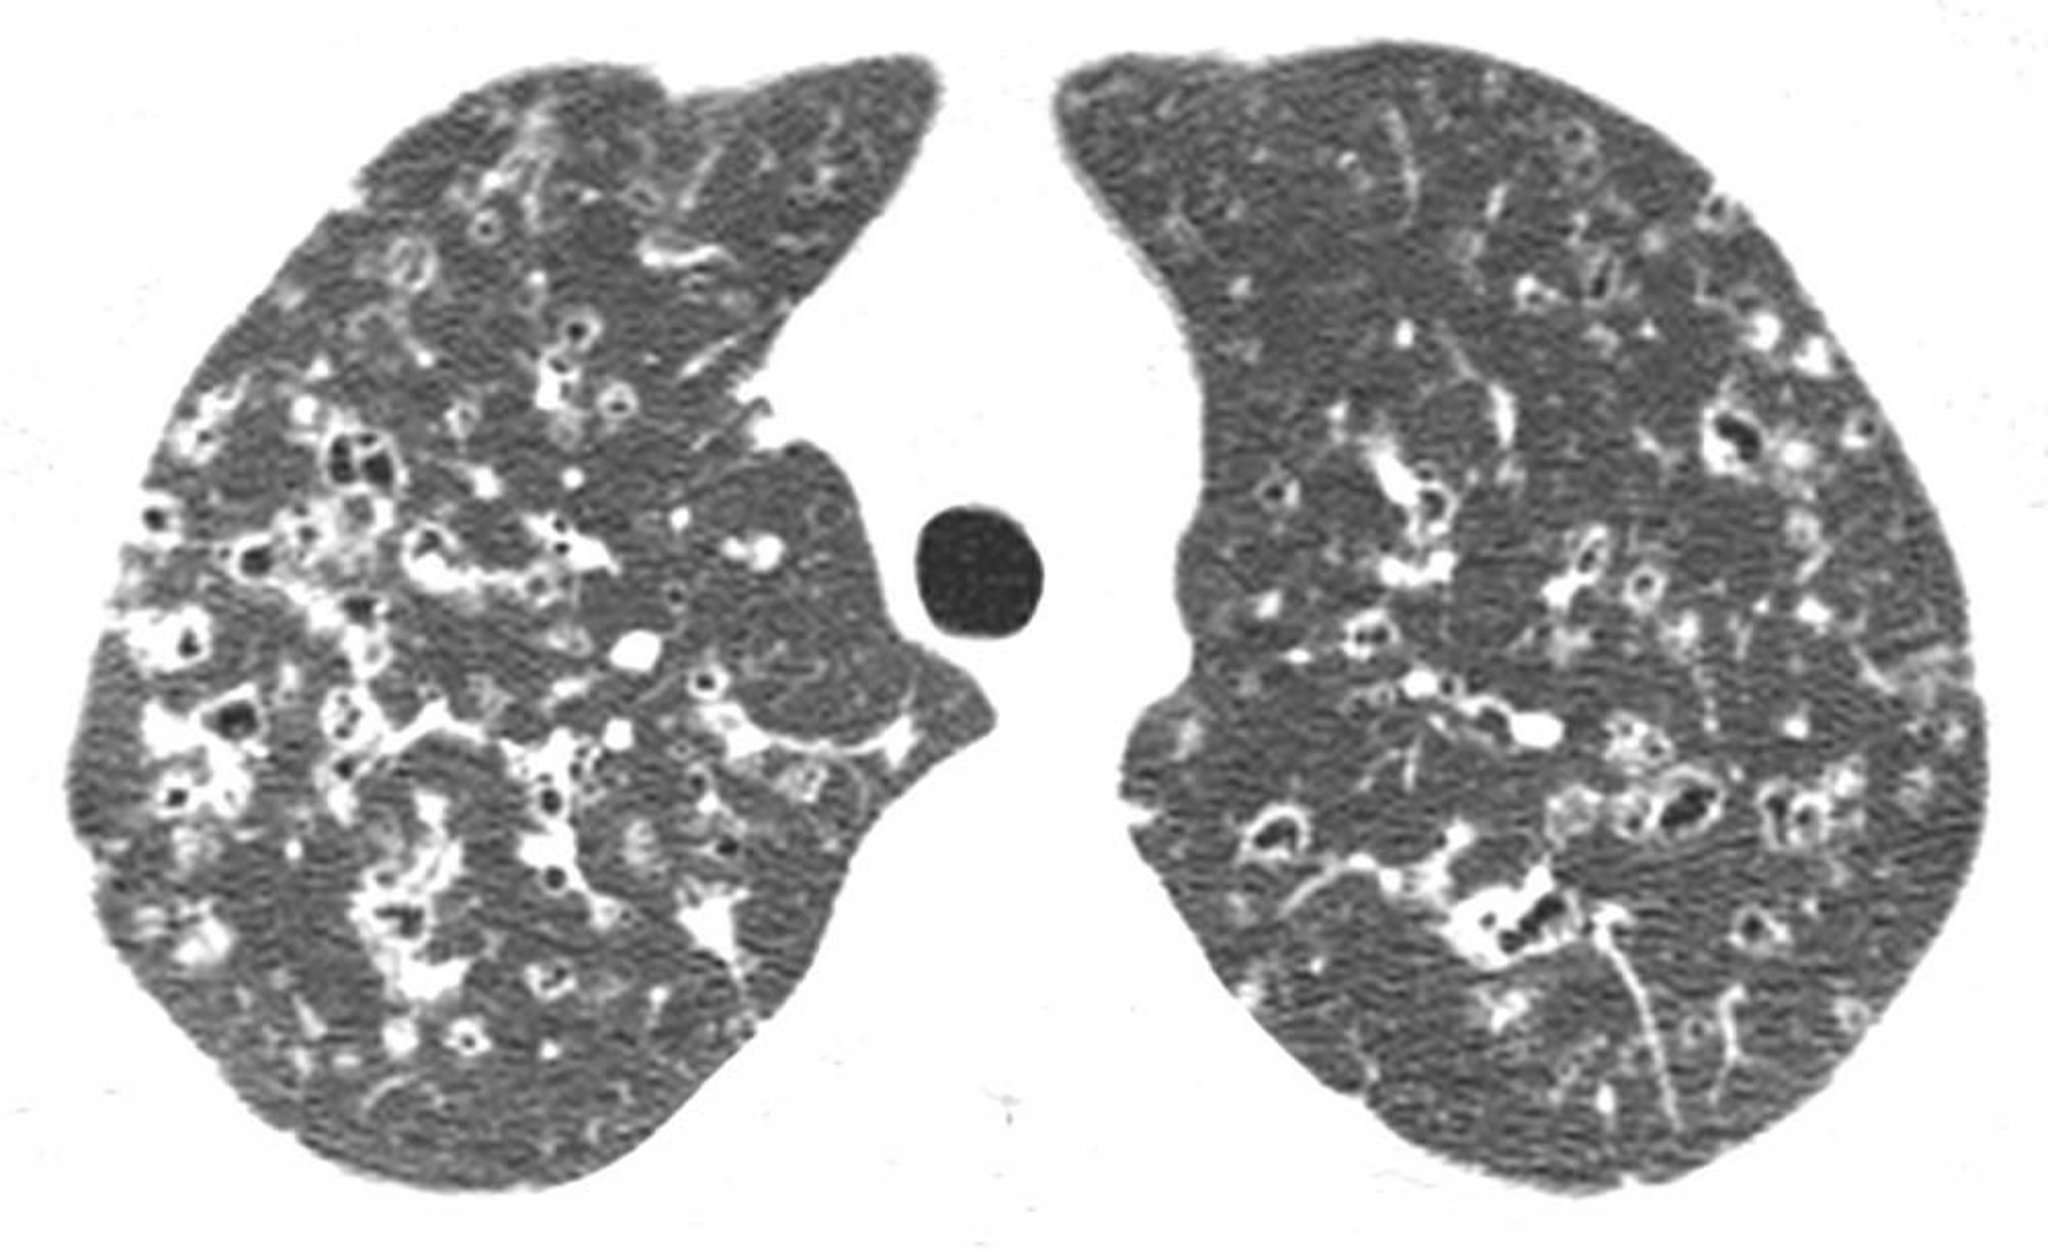

Наличие кист в средней и верхних долях (часто причудливой формы) и/или очаговых образований с утолщением интерстиция по данным КТВР считается патогномоничным для ПГЛ.

Image courtesy of Harold R. Collard, MD.